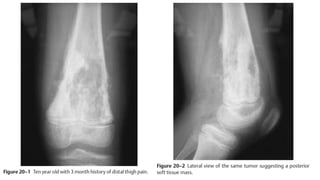

OSTEOSARCOMA DISTAL FEMUR

• A 10-year-old boy presents with a 3-month history of a painful left knee.

Before the onset of his pain, he was a fully functional youth, riding

horses and working on his parents’ ranch. He now presents in a

wheelchair with a painful, swollen left knee; examination is difficult

secondary to his extreme pain. Radiographic presentation includes plain

X-rays and a magnetic resonance image (MRI) of the knee.

OSTEOSARCOMA DISTAL FEMUR •A 10-year-old boy presents with a 3-month history of a painful left knee. Before the onset of his pain, he was a fully functional youth, riding horses and working on his parents’ ranch. He now presents in a wheelchair with a painful, swollen left knee; examination is difficult secondary to his extreme pain. Radiographic presentation includes plain X-rays and a magnetic resonance image (MRI) of the knee.